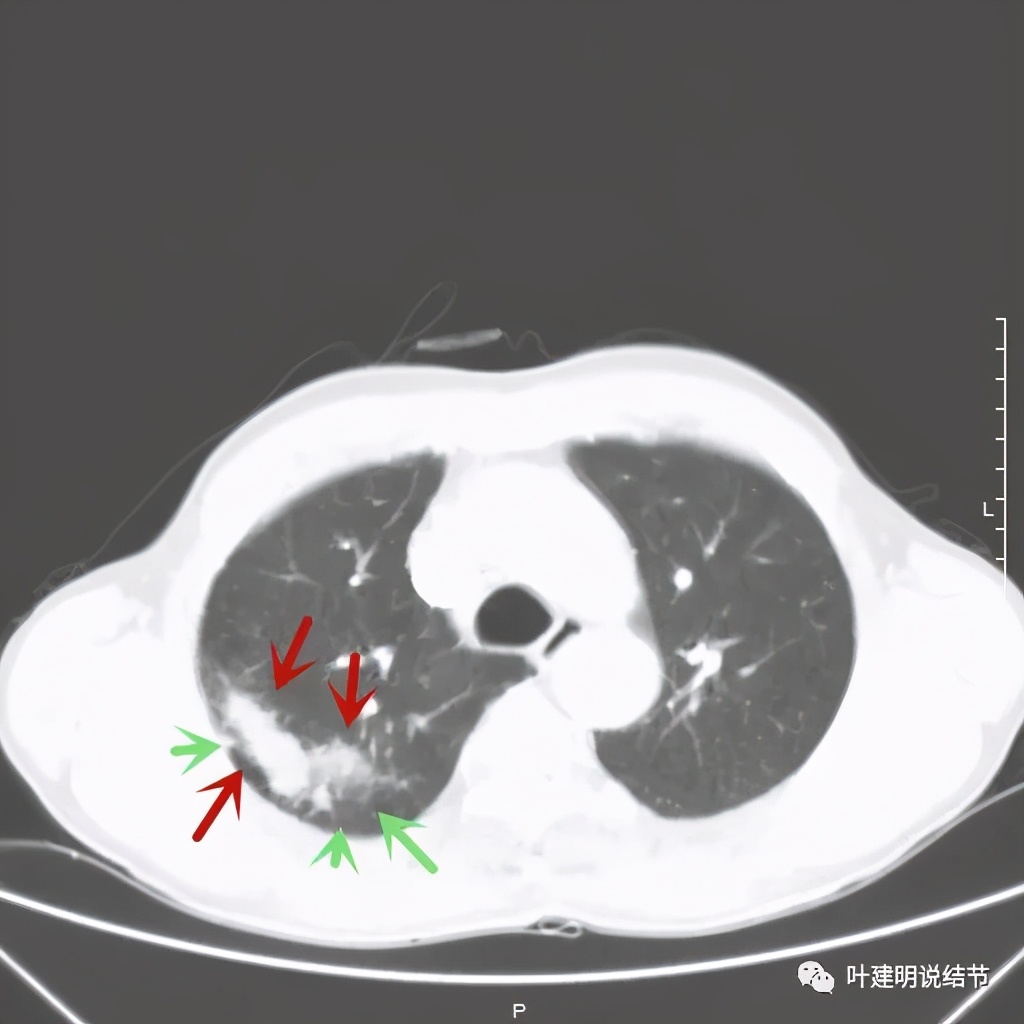

金华的某A,今年66岁,前几天在当地医院查胸部CT平扫发现右上肺占位,当时来找我看时,我想首先肺内占位是要警惕肺癌的,建议其住院进一步做增强CT,以及完善其他相关检查。其中增强CT报告示:右上叶约7*6厘米的肿块,增强后显著强化。而且某A曾于2018年5月在本院做过肺部CT,当时右上肺没有病灶的。我们先来看这次的CT图像:

红色示病灶,绿色示病灶旁边有磨玻璃成分,但较为模糊;蓝色箭头示病灶与胸膜间有牵拉,但力度不太够。

总体上感觉,病灶比较大,不规则,不是圆形或圆形生长,周围有模糊磨玻璃影(考虑炎性渗出性?),虽有胸膜牵拉,但力度不够;增强有显著强化。病灶明显却无明显临床症状,普通感染是不像的,要么是结核,要么是肺癌。但肺癌的话,在2年前没有,2年内长到这么大,恶性程度应该很高,但其纵隔淋巴结却没有明显肿大。而且病灶的边缘部分过于光滑,没有见到肿瘤的细毛刺,膨胀性也不够。整体看病灶有点像“腰子”形,弯弯曲曲的。所以我的感觉更倾向结核性。查了肿瘤筛查指标如下: